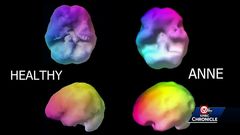

Alzheimer's Disease is a progressive, neurodegenerative disease characterized by loss of function and death of nerve cells in several areas of the brain leading to loss of cognitive function such as memory and language.